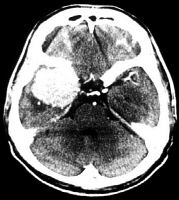

Refer to the picture above for question 3

3. Systemic associations include: